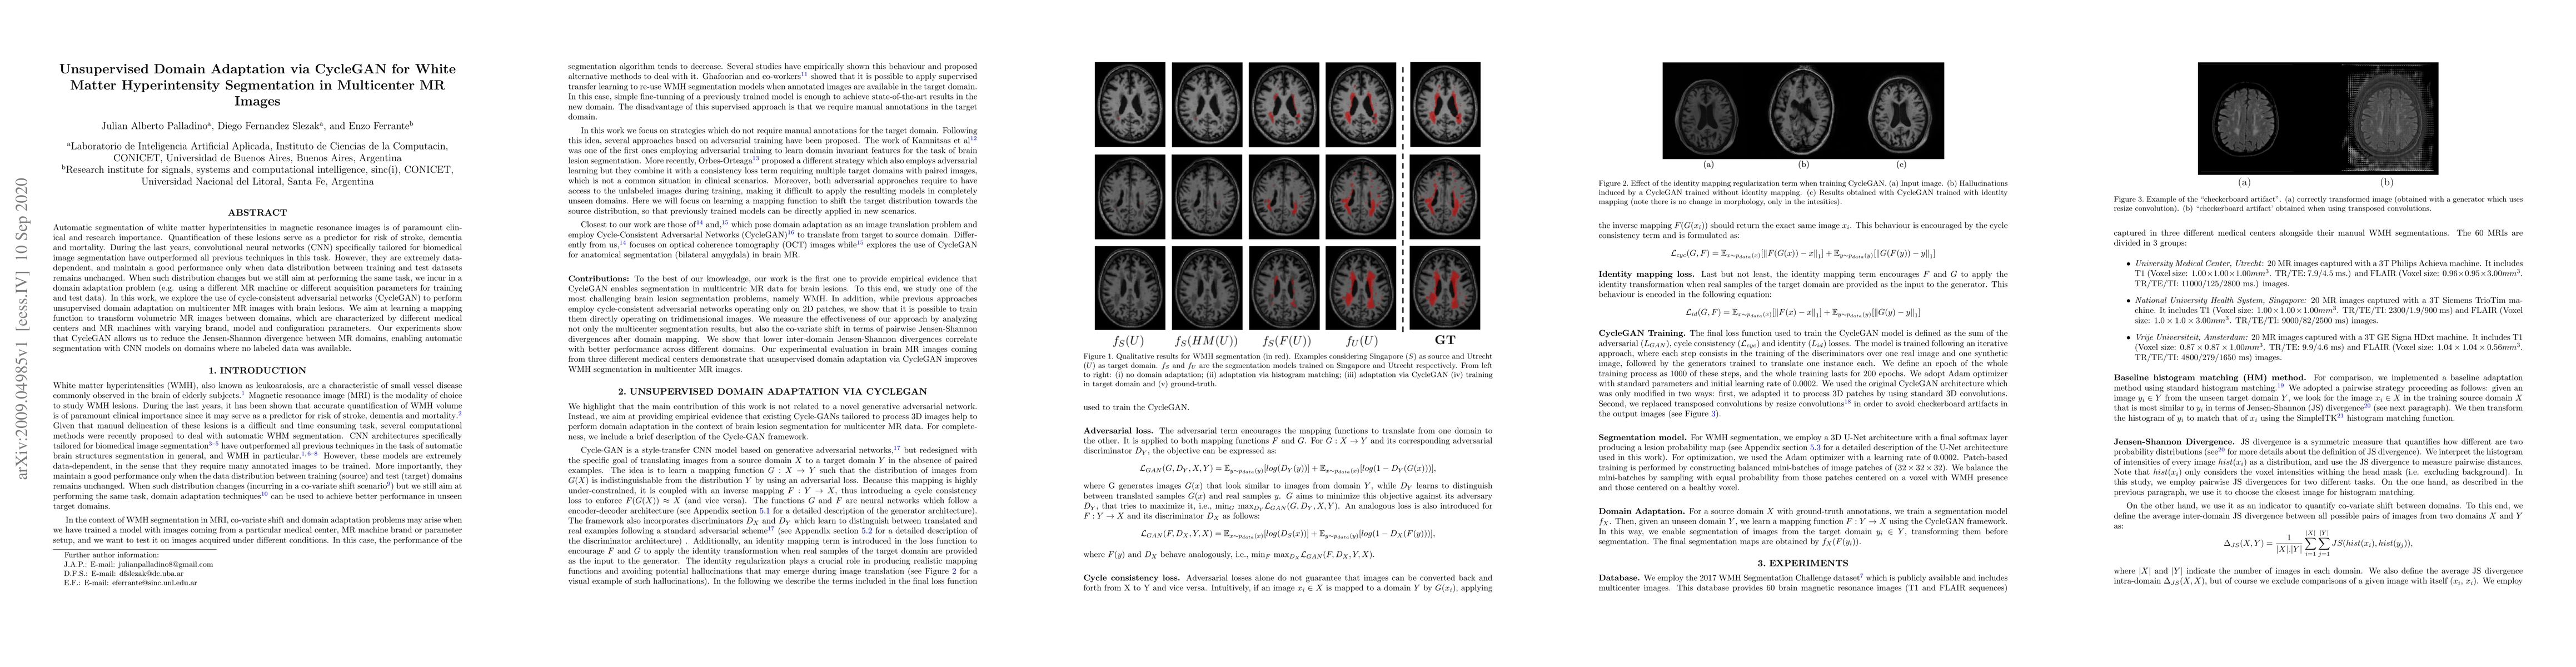

Automatic segmentation of white matter hyperintensities in magnetic resonance images is of paramount clinical and research importance. Quantification of these lesions serve as a predictor for risk of stroke, dementia and mortality. During the last years, convolutional neural networks (CNN) specifically tailored for biomedical image segmentation have outperformed all previous techniques in this task. However, they are extremely data-dependent, and maintain a good performance only when data distribution between training and test datasets remains unchanged. When such distribution changes but we still aim at performing the same task, we incur in a domain adaptation problem (e.g. using a different MR machine or different acquisition parameters for training and test data). In this work, we explore the use of cycle-consistent adversarial networks (CycleGAN) to perform unsupervised domain adaptation on multicenter MR images with brain lesions. We aim at learning a mapping function to transform volumetric MR images between domains, which are characterized by different medical centers and MR machines with varying brand, model and configuration parameters. Our experiments show that CycleGAN allows us to reduce the Jensen-Shannon divergence between MR domains, enabling automatic segmentation with CNN models on domains where no labeled data was available.